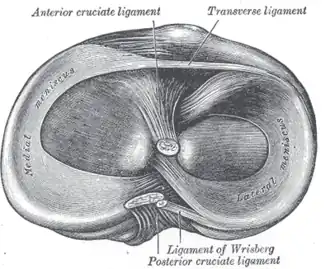

| Head of right tibia seen from above, showing menisci and attachments of ligaments | |

There are two menisci in the knee. They sit between the thigh bone and the shin bone. While the ends of the thigh bone and the shin bone have a thin covering of soft hyaline cartilage, the menisci are made of tough fibrocartilage and conform to the surfaces of the bones they rest on. One meniscus rests on the medial tibial plateau; this is the medial meniscus. The other meniscus rests on the lateral tibial plateau; this is the lateral meniscus.[3][4]

Anatomy

The menisci are C-shaped wedges of fibrocartilage located between the tibial plateau and femoral condyles. The menisci contain 70% type I collagen.[10] The larger semilunar medial meniscus is attached more firmly than the loosely fixed, more circular lateral meniscus. The anterior and posterior horns of both menisci are secured to the tibial plateaus. Anteriorly, the transverse ligament connects the 2 menisci; posteriorly, the meniscofemoral ligament helps stabilize the posterior horn of the lateral meniscus to the femoral condyle. The coronary ligaments connect the peripheral meniscal rim loosely to the tibia. Although the lateral collateral ligament (LCL) passes in close proximity, the lateral meniscus has no attachment to this structure.[10]

The joint capsule attaches to the entire periphery of each meniscus but adheres more firmly to the medial meniscus. An interruption in the attachment of the joint capsule to the lateral meniscus, forming the popliteal hiatus, allows the popliteus tendon to pass through to its femoral attachment site. Contraction by the popliteus during knee flexion pulls the lateral meniscus posteriorly, avoiding entrapment within the joint space. The medial meniscus does not have a direct muscular connection. The medial meniscus may shift a few millimeters, while the less stable lateral meniscus may move at least 1 cm.